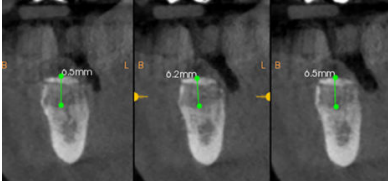

Cinco meses después, se efectuó un nuevo CBCT para evaluar la ganancia ósea conseguida. En el estudio tomográfico pudo observarse una ganancia media vertical de 6,4 mm y una ganancia media horizontal de 7,8 mm, lo que sumado al hueso remanente permitió colocar dos implantes Klockner® KL RP de 4 x 10 mm en 46 y 47 a 35 N/cm2 (Figuras 8-12). El diente 45 se decidió rehabilitar mediante un póntico en extensión para prevenir la lesión del nervio mentoniano durante la inserción de los implantes. La segunda fase se realizó a los tres meses de su colocación. Tras la cicatrización del tejido blando, se tomaron las impresiones mediante el escáner intraoral Carestream Dental CS 3600 y se realizaron las restauraciones protésicas finales con tecnología CAD/CAM (Figuras 13 y 14).